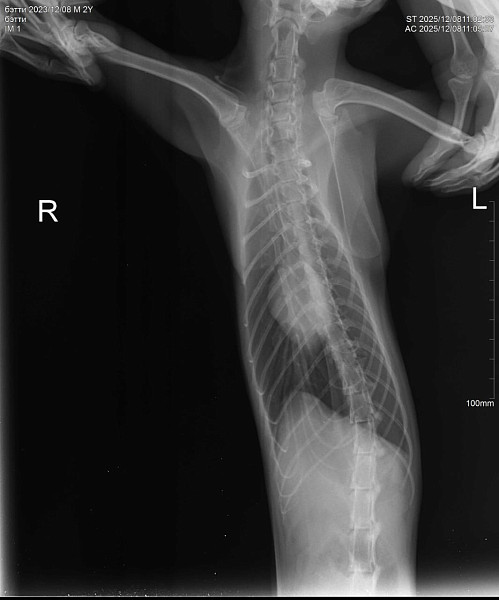

Здравствуйте! У нас кошка 10 дней находилась на улице. Через 10 дней вернулась никакая, сильное истощение, дезориентация. Кошка ходит и стукаетсях, как будто потеря в пространстве. Самостоятельно питаться не может. Повезли в ветеринарке, сделали рентген, говорят возможно ЧМТ или оттек головного мозга. Выписали препараты. Кормим со шприца, сейчас уже чуть бодрее стала, дней пять прошло после визита в ветеринару. Аппетит хороший. Но самостоятельно есть не может, зрительный рефлекс слабый. Глазки чистые.